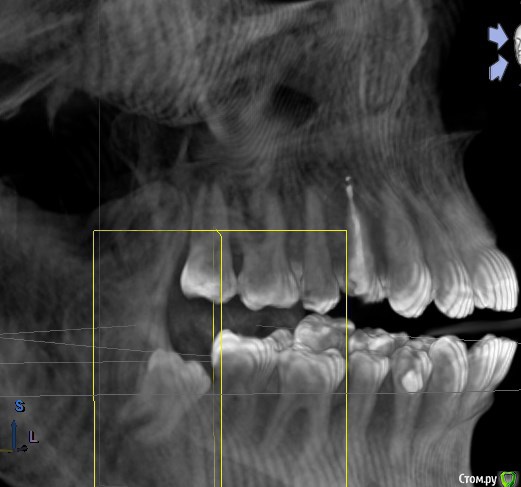

(Есть также файл КТ до удаления, но я хз, что из него надо брать, так что заскринила, что смогла).

post-60858-0-95972000-1596146826_thumb.jpg